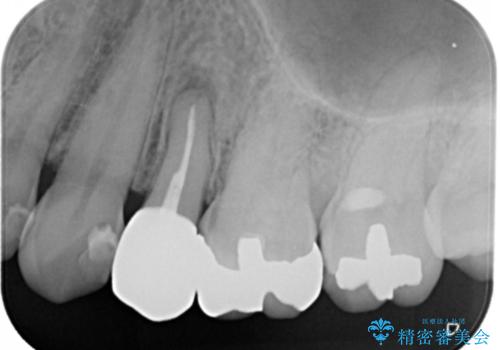

セラミックでの治療を希望されたので、フルジルコニアクラウンでの治療を選択しました。

治療後は症状も無くなり経過は良好です。